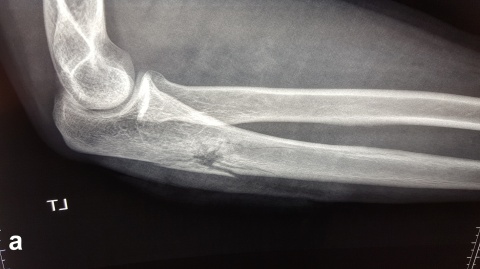

Es zeigt sich das typische Bild einer Schussfraktur nach Niedrigenergieverletzung. a seitlicher Strahlengang,

b a. p. Strahlengang

Beim Auftreffen des Projektils im Rahmen von Niedrigenergieverletzungen auf Knochengewebe entsteht meist eine typische, einfache Fraktur (Abbildung 2). Hochenergieverletzungen des Knochens münden in eine multifragmentäre Situation, bei der ein Großteil der Projektilenergie an den Knochen abgegeben wird. Insbesondere lange Röhrenknochen können, da sie wie eine starre, spröde flüssigkeitsgefüllte Röhre agieren, durch Projektile mit hoher Energie explosionsartig zerstört werden (Abbildung. 3).